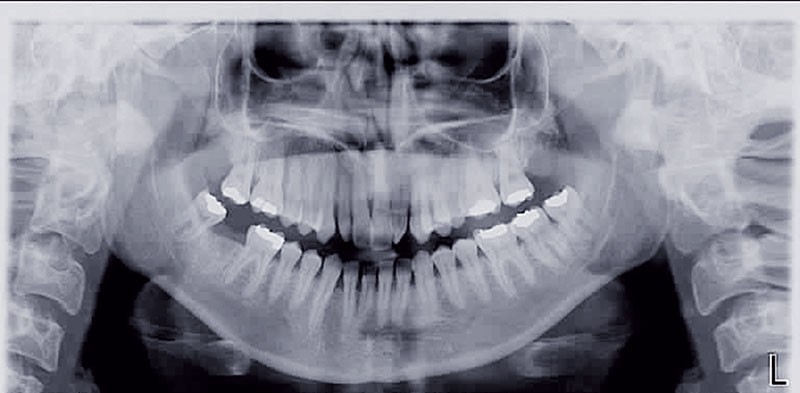

Cette patiente est venue consulter pour son occlusion inversée et ses importantes malpositions dentaires antérieures associées à la perte d’une dent et à des problèmes parodontaux.

• Malocclusion de classe III d’Angle par rétroalvéolie maxillaire,

• endoalvéolie maxillaire avec occlusion inversée antérieure et bilatérale,

• infraclusion incisive,

• fortes malpositions des incisives supérieures (dont 22 qui est en rotation axiale disto-palatine de 90°), • dysharmonie dento-dentaire (12 en « grain de riz » est aussi en rotation marginale disto-palatine de 45°),

• anomalie de la forme d’arcade maxillaire, 47, 18 et 28 sont absentes. (fig. 1 à 8), 48 est positionnée très postérieurement, quasiment au niveau de la branche montante (fig. 9 et 11).

Sur le plan parodontal, il existe une gingivite résiduelle à une gingivectomie (la patiente étant sous anti-épileptiques).

Après assainissement parodontal, un traitement par expansion maxillaire avec vestibuloversion des incisives supérieures et mésialisation de 48 en lieu et place de 47 a été choisi. Il a été décidé d’extraire 38. Afin de permettre une reconstitution prothétique pour compenser la microdontie de 12 il est prévu de laisser un espace de part et d’autre de celle-ci, équivalent au diamètre mésio-distal de 22 soit 6,5 mm.